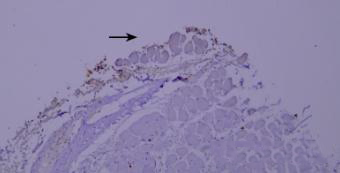

7.干片

干片导致的假阴性(黑色箭头区域)。

优化建议:

加入Tween-20的缓冲液能够更好地防止切片干燥。